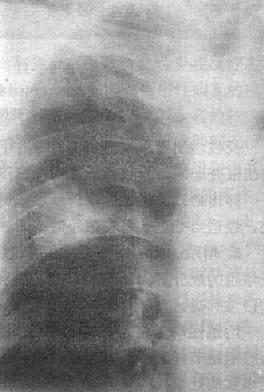

图3-1-24 左肺浸润型肺结核空洞形成

左肺上野第2前肋间边缘模糊的致密影,其中可见空洞